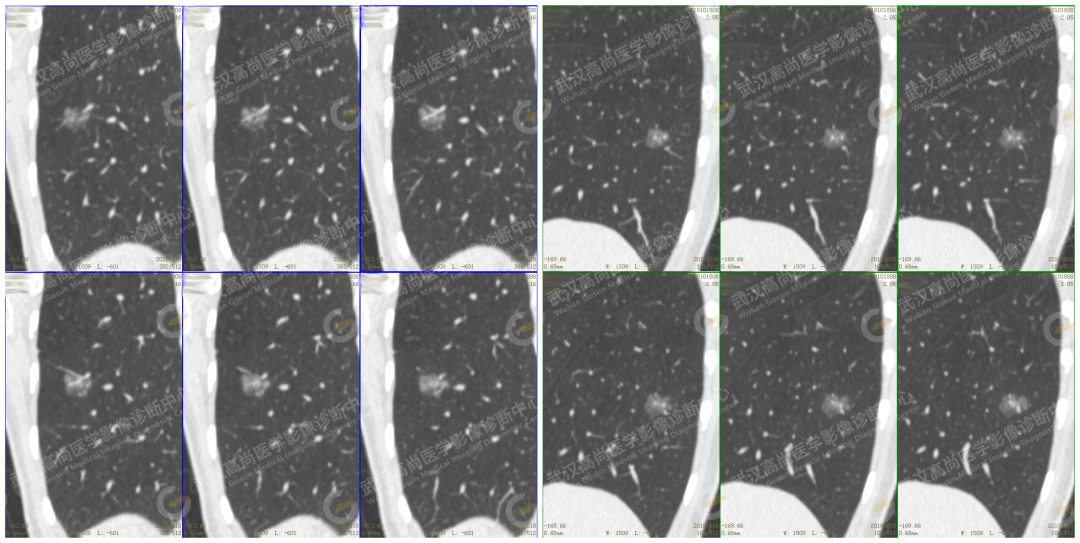

PET/CT:混合磨玻璃结节 mGGN SUVmax6.4 SUVmin5.0

CT 示:实性成分占比 80% 左右 mGGN,磨玻璃边缘清楚,浅分叶,见小空泡、血管集束征,支气管及血管穿行其中